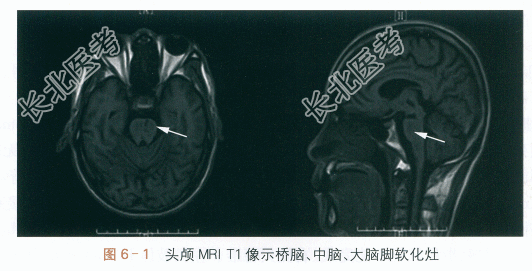

(2)头颅MRI:桥脑、中脑、大脑脚梗死后遗片状脑软化灶,如图6-1所示。